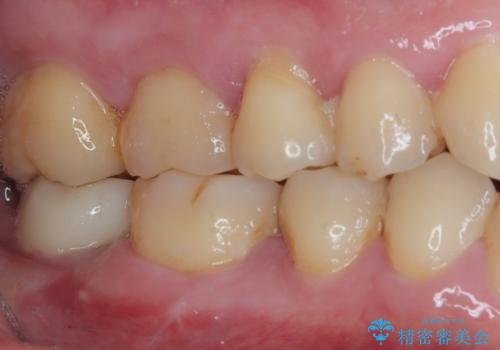

部分矯正を行ったこと治療期間は長くなりましたが、違和感のない咬み合わせを達成することができました。